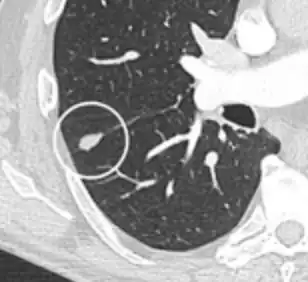

A lung nodule or pulmonary nodule is a relatively small focal density in the lung. A solitary pulmonary nodule (SPN) or coin lesion,[1] is a mass in the lung smaller than three centimeters in diameter. A pulmonary micronodule has a diameter of less than three millimetres.[2] There may also be multiple nodules.

One or more lung nodules can be an incidental finding found in up to 0.2% of chest X-rays[3] and around 1% of CT scans.[4]

The nodule most commonly represents a benign tumor such as a granuloma or hamartoma, but in around 20% of cases it represents a malignant cancer,[4] especially in older adults and smokers. Conversely, 10 to 20% of patients with lung cancer are diagnosed in this way.[4] If the patient has a history of smoking or the nodule is growing, the possibility of cancer may need to be excluded through further radiological studies and interventions, possibly including surgical resection. The prognosis depends on the underlying condition.